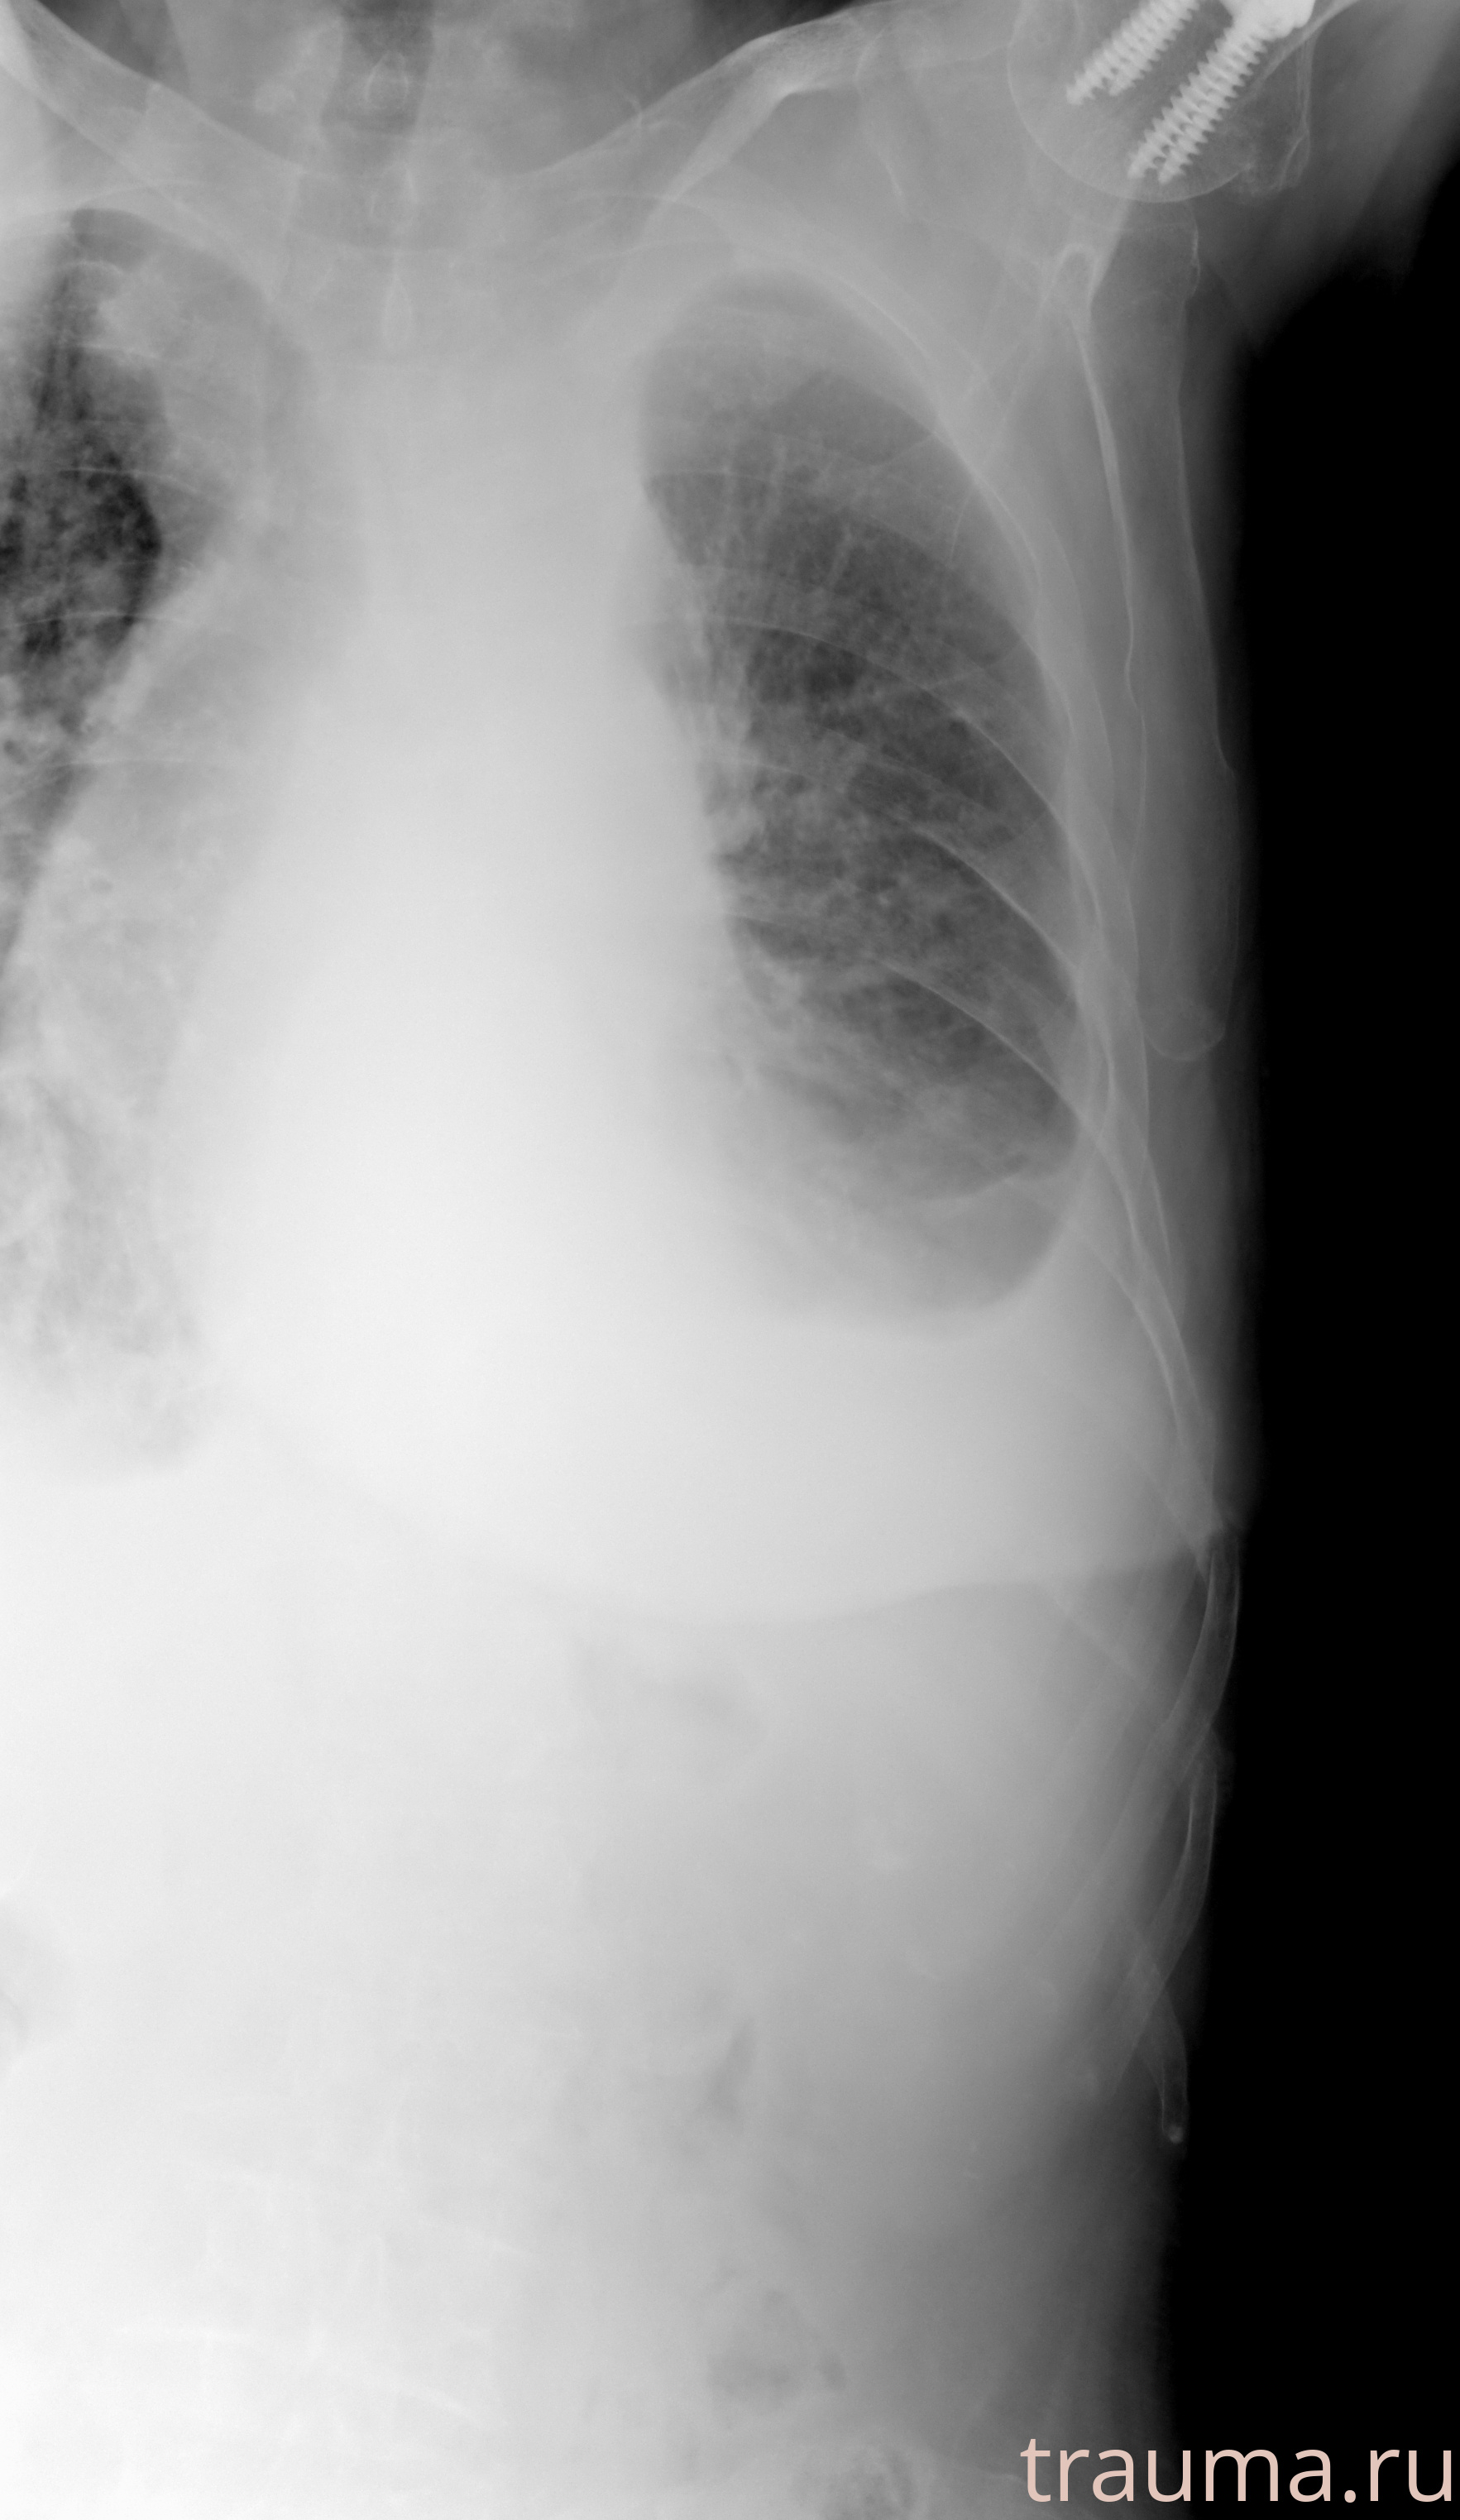

Рентген на дому: по вашему адресу приезжает врач-рентгенолог, травматолог-ортопед с мобильным рентгеновским аппаратом, проводит диагностику травмы или заболевания, делает необходимые рентгенограммы, дает рекомендации по дальнейшему лечению. Получить качественные снимки в домашних условиях возможно благодаря уникальной методике, разработанной МосРентген Центром для института  Склифосовского